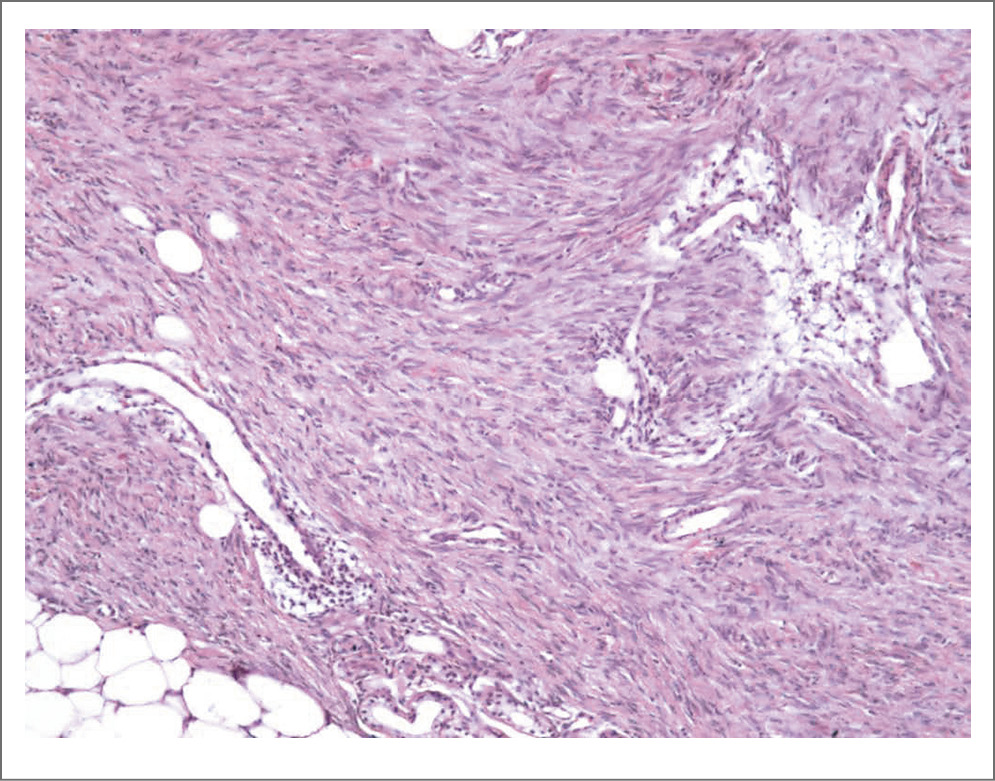

Данные патогистологического исследования. В биоптате кожи эпидермис не изменен. В средних и глубоких отделах дермы (без вовлечения поверхностных отделов), с переходом на ПЖК, имеются разрастания мономорфных веретеновидных клеток с овальными и извитыми ядрами и умеренным количеством цитоплазмы, которые ориентированы параллельно эпидермису. Местами клетки образуют завихрения. Митозы единичные. Границы опухоли нечеткие. Адипоциты проксимальных отделов ПЖК расположены в виде ячеистой структуры среди опухолевых клеток (рис. 2–5). Данные ИГХ-исследования: диффузное окрашивание CD34++ (рис. 6), Desmin-, SMA-, S100-, CD68-, Melan A-, Ki-67 – 8%. Установлен диагноз: дерматофибросаркома выбухающая, классический вариант. Пациентка направлена к онкологу для удаления опухоли.

Рис. 2. В средних и глубоких отделах дермы (без вовлечения поверхностных отделов) видны разрастания веретеновидных клеток, ориентированных параллельно эпидермису (окраска гематоксилином и эозином, ×50).

Рис. 3. Разрастания веретеновидных клеток с овальными и извитыми ядрами в глубоких отделах дермы с переходом на ПЖК. Адипоциты в виде ячеек располагаются среди опухолевых клеток; последние окружают и сдавливают придатки кожи (потовые железы; окраска гематоксилином и эозином, ×100).

Рис. 4. Большее увеличение дистального края опухоли (окраска гематоксилином и эозином, ×200).

Рис. 5. Веретеновидные клетки опухоли с извитыми ядрами, мономорфные, с умеренным количеством цитоплазмы. Адипоциты в виде ячеек располагаются среди опухолевых клеток (окраска гематоксилином и эозином, ×400).